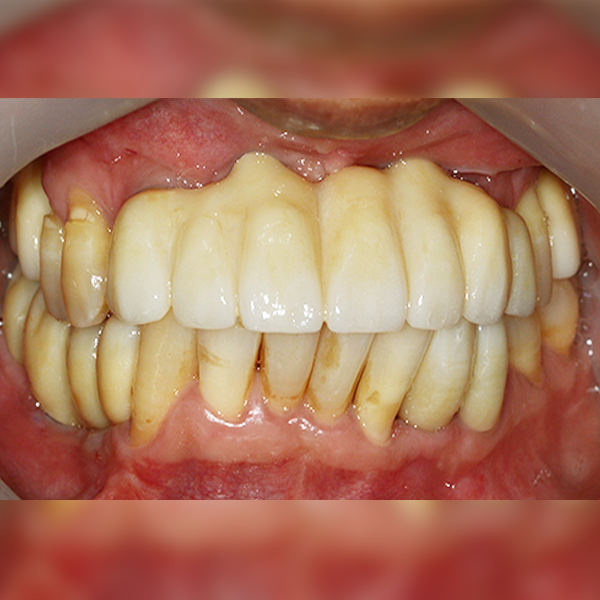

上顎/臼齒部位 / 3顆以下 / 補骨|舒眠

案例 188 50多歲 陳*英 2020-02-06 / 2020-12-11